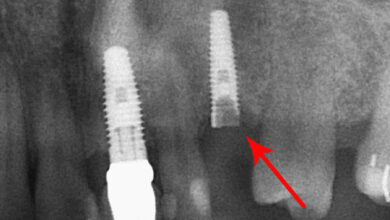

در هر جلسه جراحی چند ایمپلنت می توان کاشت؟

کاشت ایمپلنت دندان به عنوان استاندارد طلایی برای جایگزینی دندانهای از دست رفته شناخته میشود. اما یکی از اولین و مهمترین سوالاتی که برای بیماران مطرح میشود این است که: چند ایمپلنت را میتوان در یک جلسه جراحی کاشت؟ پاسخ به این سوال یک عدد ثابت نیست، بلکه یک تصمیم بالینی پیچیده است که به عوامل متعددی از جمله سلامت…

در صورت شکستن پیچ داخل ایمپلنت چه باید کرد؟

راهنمای کامل مدیریت و خارج کردن پیچ شکسته داخل ایمپلنت ایمپلنتهای دندانی به عنوان استاندارد طلایی برای جایگزینی دندانهای از دست رفته شناخته میشوند و با نرخ موفقیت بسیار بالا، لبخند و کیفیت زندگی را به میلیونها نفر بازگرداندهاند. با این حال، مانند هر سیستم مهندسی پیشرفتهای، این ساختارها نیز ممکن است با چالشهای فنی روبرو شوند. یکی از مشکلات…